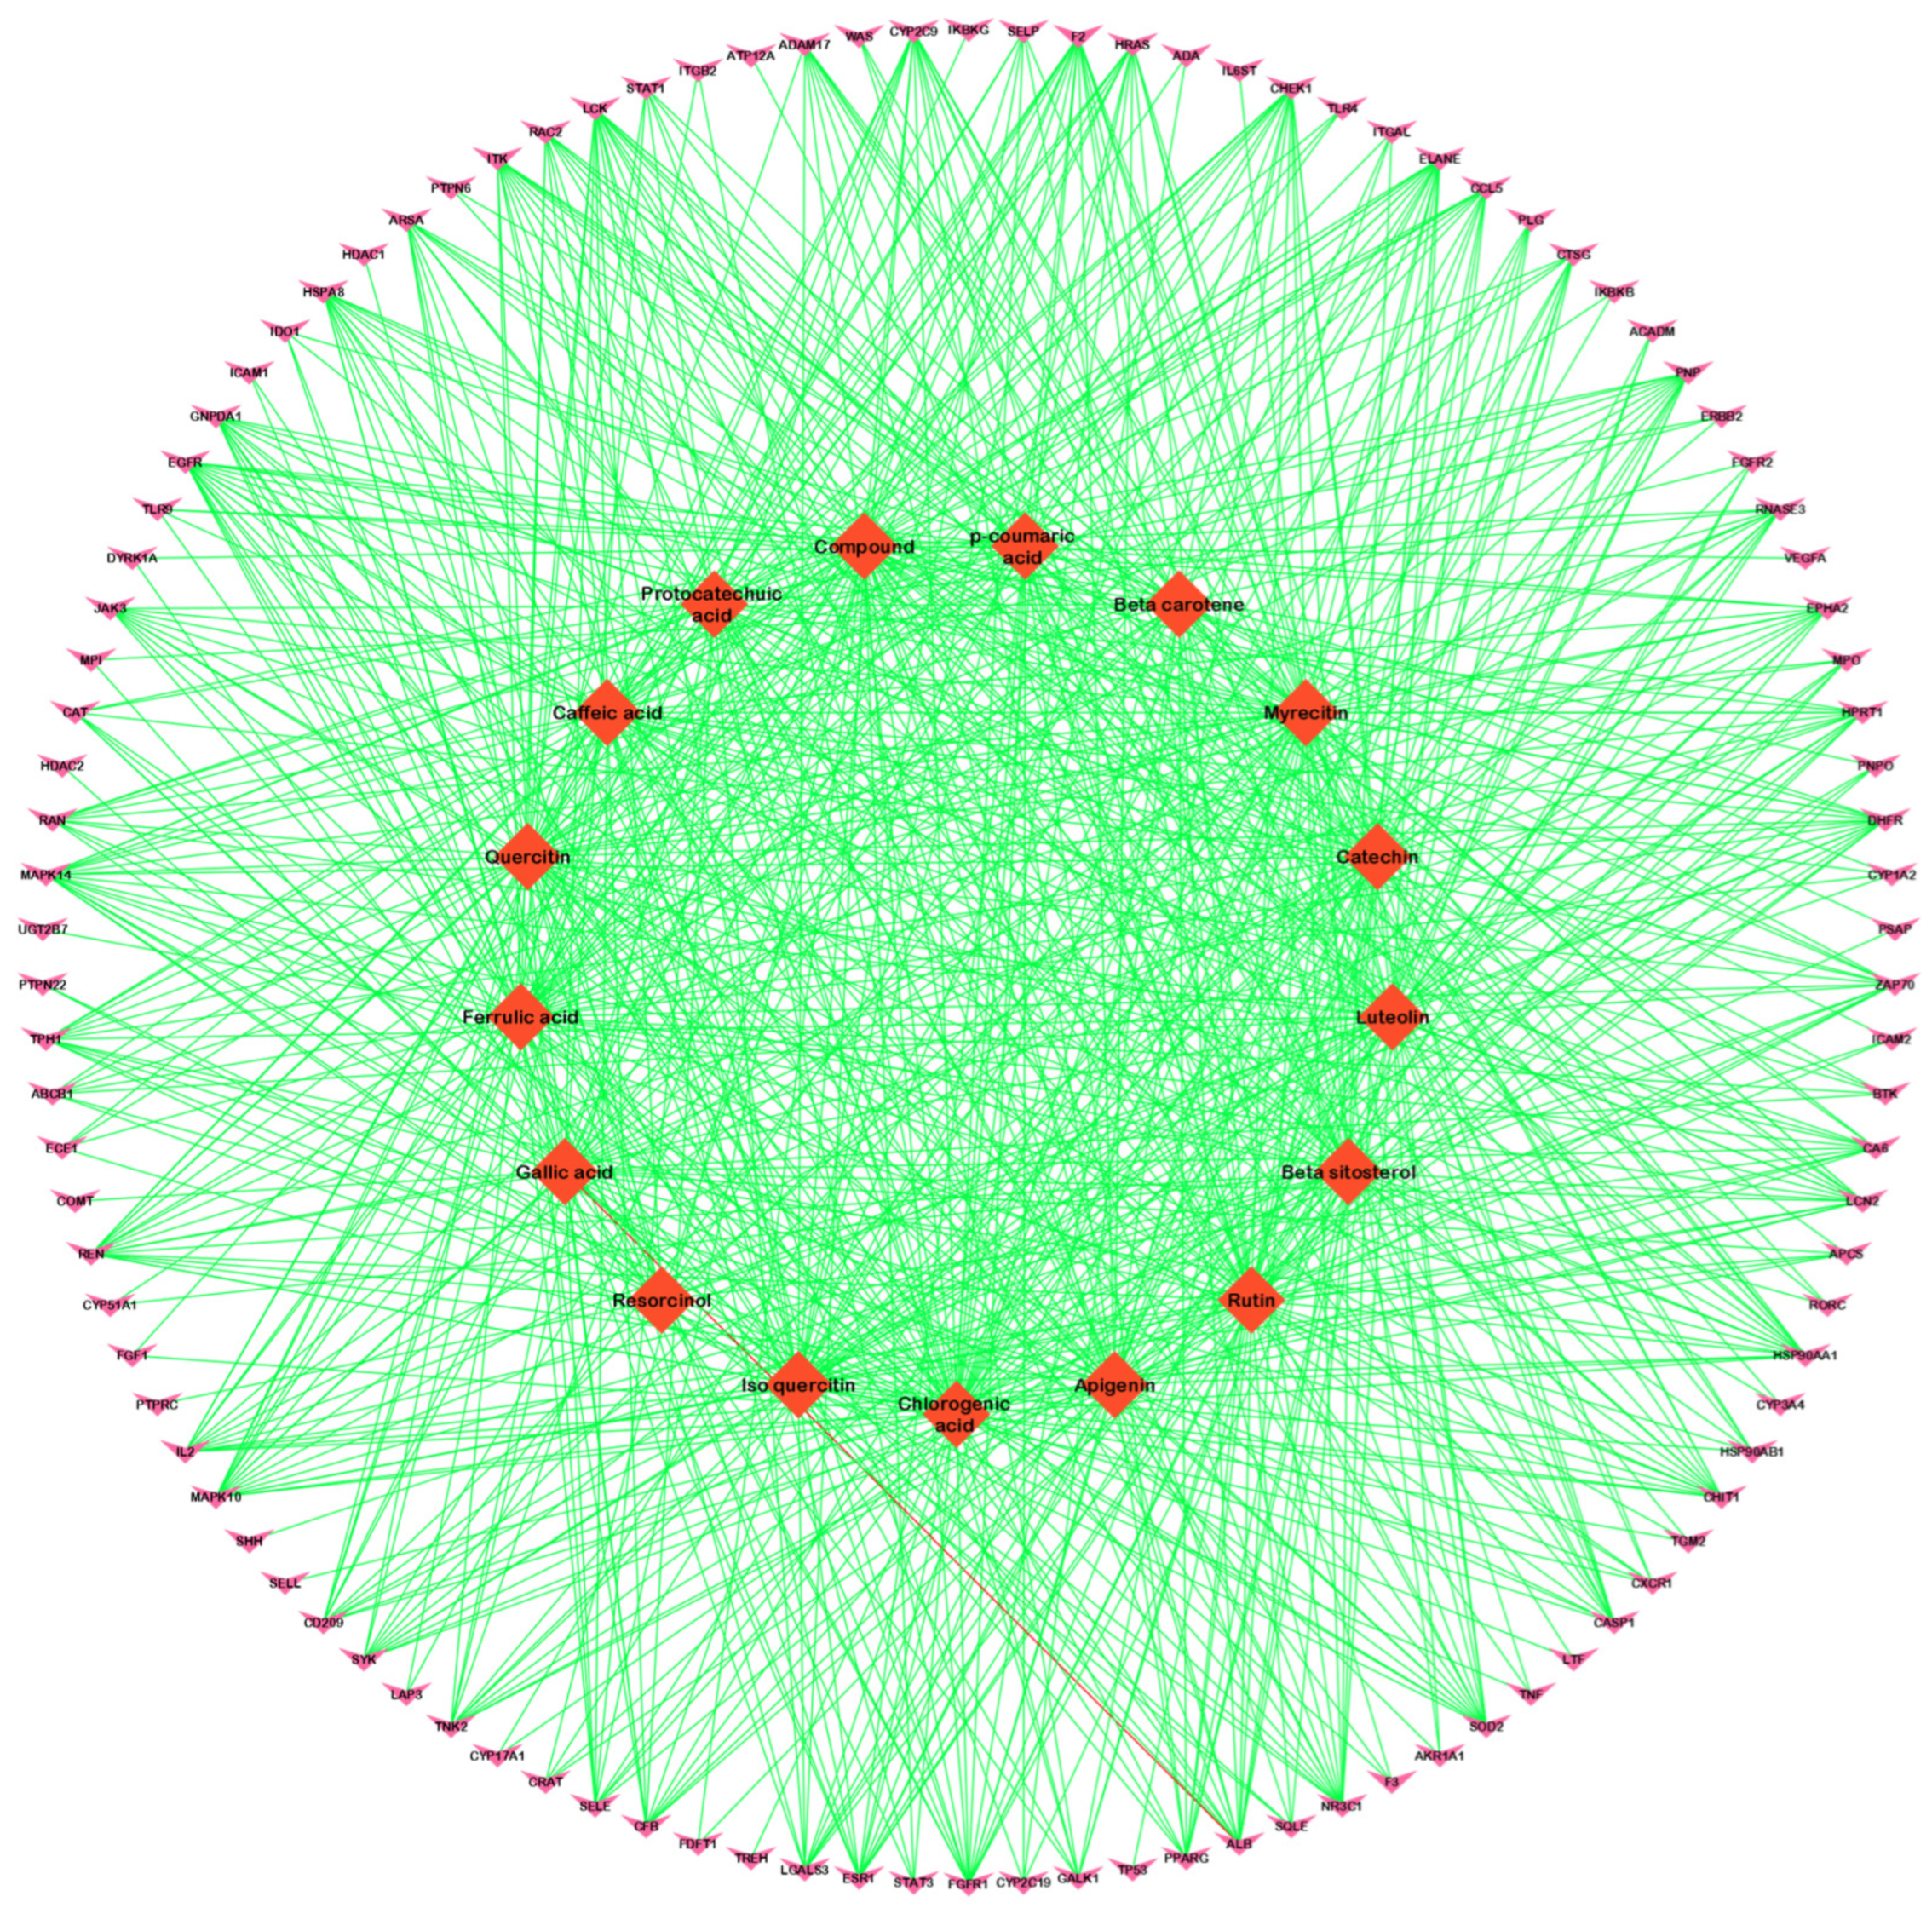

3.2. Compound–Disease Common Target Network Construction and Analysis

3.3. Analysis of Functional and Pathway Enrichment